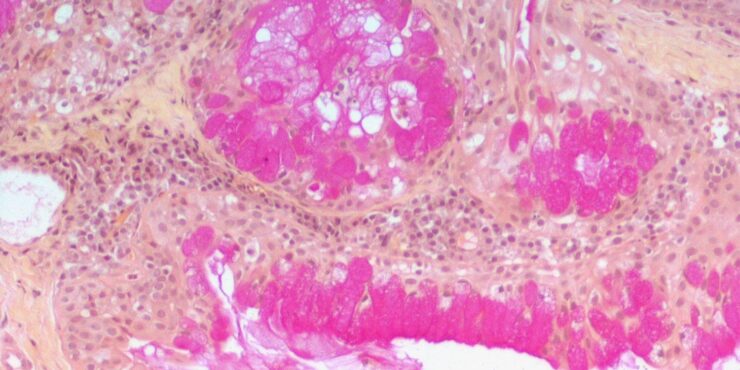

Mucinous eccrine carcinoma = الكارسينوم المخاطيني الناتح

Mucinous eccrine carcinoma = الكارسينوم المخاطيني الناتح MUCINOUS CARCINOMA Epidemiology. Primary mucinous carcinoma of the skin (colloid, gelatinous, or adenocystic carcinoma) is a rare, low-grade carcinoma. Etiology. This lesion bears close morphologic resemblance to mucinous carcinoma of the breast. Clinical Findings. It presents as a solitary, slowly growing, soft to firm, grayish, reddish, or bluish […]